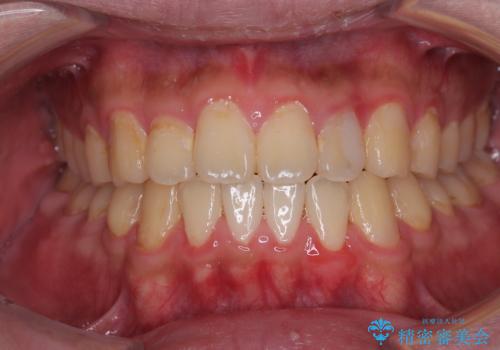

気になっていたクロスバイトは速やかに改善され、1年間で治療を終えることができました。

治療開始前は汚れが多く、全体的に歯肉が腫れていましたが、矯正治療を通して腫れも少しずつ改善されました。